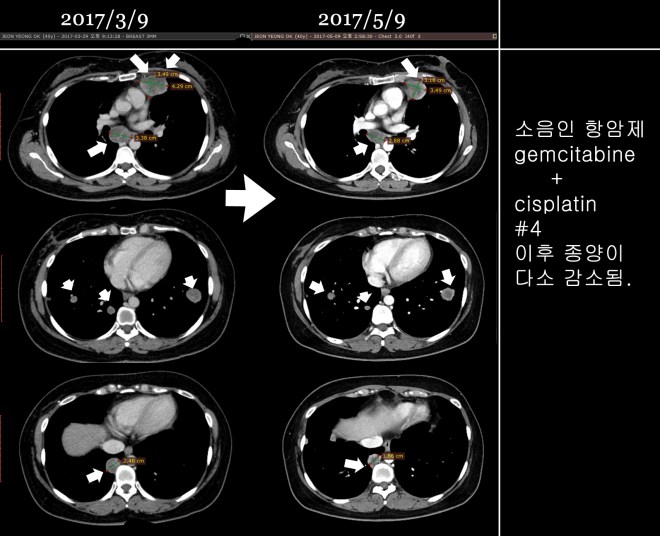

• 2017.3.31- 2017.5.15까지 – gemcitabine+cisplatin 결합요법 시행

• 3차까지는 호전반응을 보이다가 4차(5/15) 이후에 chest상 종양이 약간 커진 것을 발견하고 이 요법을 중지함

서울대로 옮겨서 7 차 이후에 12 차까지 택솔을 시행하고 나서 종양이 매우 급속도로 폐에 전이가 되자 주치의는 약물을 바꾸어서 소음인 약물로만 구성된 gemcitabine하고 cisplatin을  2017년 3월부터 2017년 5월까지 시행하였다. 그리고 5월달 CT는 다소 종양의 감소를 보였다.